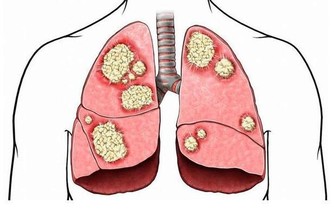

血液中的「血垢」是指膽固醇、甘油三酯等,它們在血管壁上越積越多,形成如同黃色小米粥樣的斑塊。

很多人以為,只有到老了的時候,才為我們的血管操心。殊不知,血管斑塊變大,從30歲以後就加速了。 所以,日常按照下面這樣的飲食習慣來吃,可以幫助我們改善血管健康! *****每天一盤涼拌菜*****涼拌菜可以有很多種類的蔬菜,會滿足我們人體對蔬菜的營養需求,並且在涼拌菜的時候,加點富含歐米伽3脂肪酸α-亞麻酸的蘇麻油來替代傳統的香油。